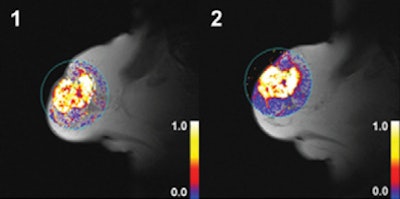

| Dynamic T1-weighted MR images of a 60-mm grade 2 breast carcinoma in the right breast of a 70-year-old woman whose disease relapsed 38.8 months after diagnosis. The patient died 47.2 months after initial radical treatment. Her tumor displayed high values for Ktrans after two cycles of chemotherapy. (1) Ktrans before treatment; (2) Ktrans after treatment. Images courtesy of Radiology. |

The researchers' univariate analysis found that the type of surgery performed and higher post-treatment Ktrans were among the significant predictors of worse disease-free survival. The same analysis concluded that clinical tumor stage and type of surgery performed were among the significant predictors of overall survival.

Patients with breast cancer "exhibiting higher levels of vascularization after two cycles of [neoadjuvant chemotherapy] experience worse disease-free and overall survival," and contrast-enhanced MRI measures of vascularity after treatment "may act as predictors of disease outcome in patients undergoing [neoadjuvant chemotherapy]," Li and colleagues concluded.